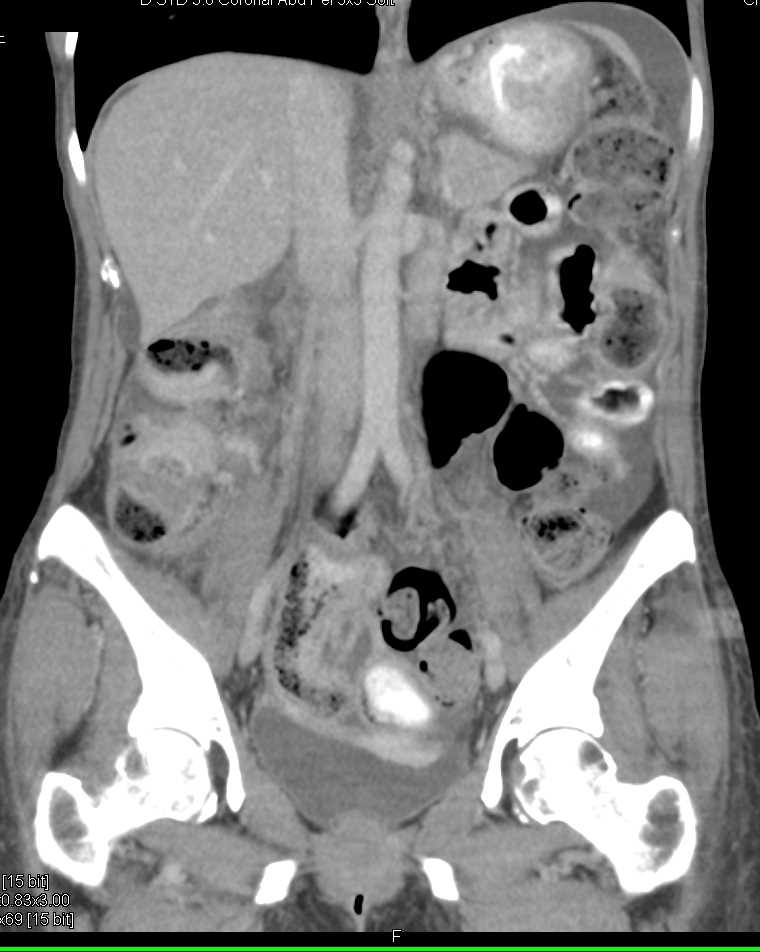

Incidental Colonic Lipoma in a Patient with Pseudomembranous Colitis (PMC)